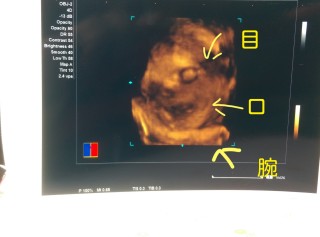

転院先が4Dエコーをやっている婦人科だったので初4D(^^) 前回までは大きめと言われていましたが今回は週数通りで順調とのことです。 親ばかになっちゃいますね(笑) 男の子です。この写真を見た人みんなに「ママ似かな?」と言われます。次回の健診が楽しみ♪

3Dエコーです。 逆子も直り、唇と鼻がクッキリ見えました。 推定体重1545gまで大きくなってくれて、安心しました。 前回まで少し小さめかな?と思っていたのですが、今回は先生から「少し大きめかもよ~」と。 このまま順調に大きくなりますように!